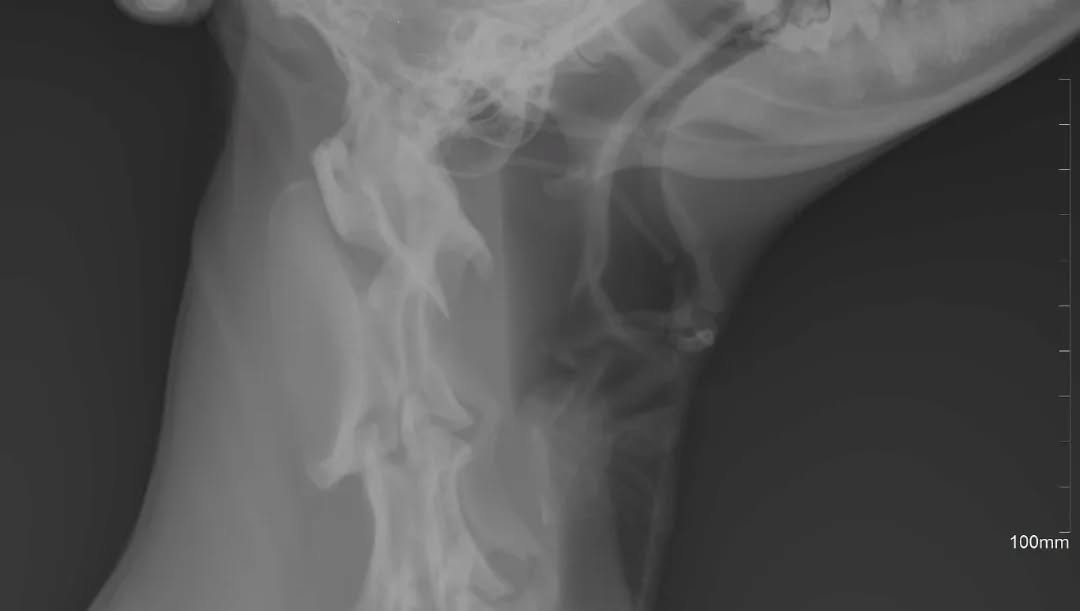

Құлан агротехникалық жоғары колледжінің ветериарлық клиникасында құмай тазыға алғашқы ветеринарлық көмек көрсетілді. Колледжің арнайы пәндер оқытушылары Рашид Сарсенбиев, Еркебұлан Ертаев, Ернұр Тасжүреков және 3 курс Ветеринария мамандығының студенттері рентген аппараты арқылы иттің мойын бөлігін зерттеп, жұтқыншағы мен өңешінің зақымданғаны анықталды. Емдеу мақсатында жануарға шұғыл ота жасалды. Ота барысында өңештің қабынған жерлері өңделді, иттің иесіне отадан кейінгі күтіп-бағу ұсыныстары берілді.